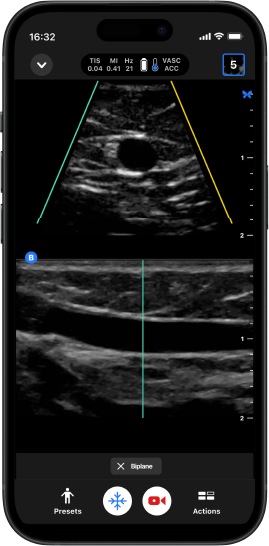

Biplano™

O primeiro POCUS Biplane Imaging portátil do mundo torna possível ver o eixo curto e longo do seu exame em tempo real.